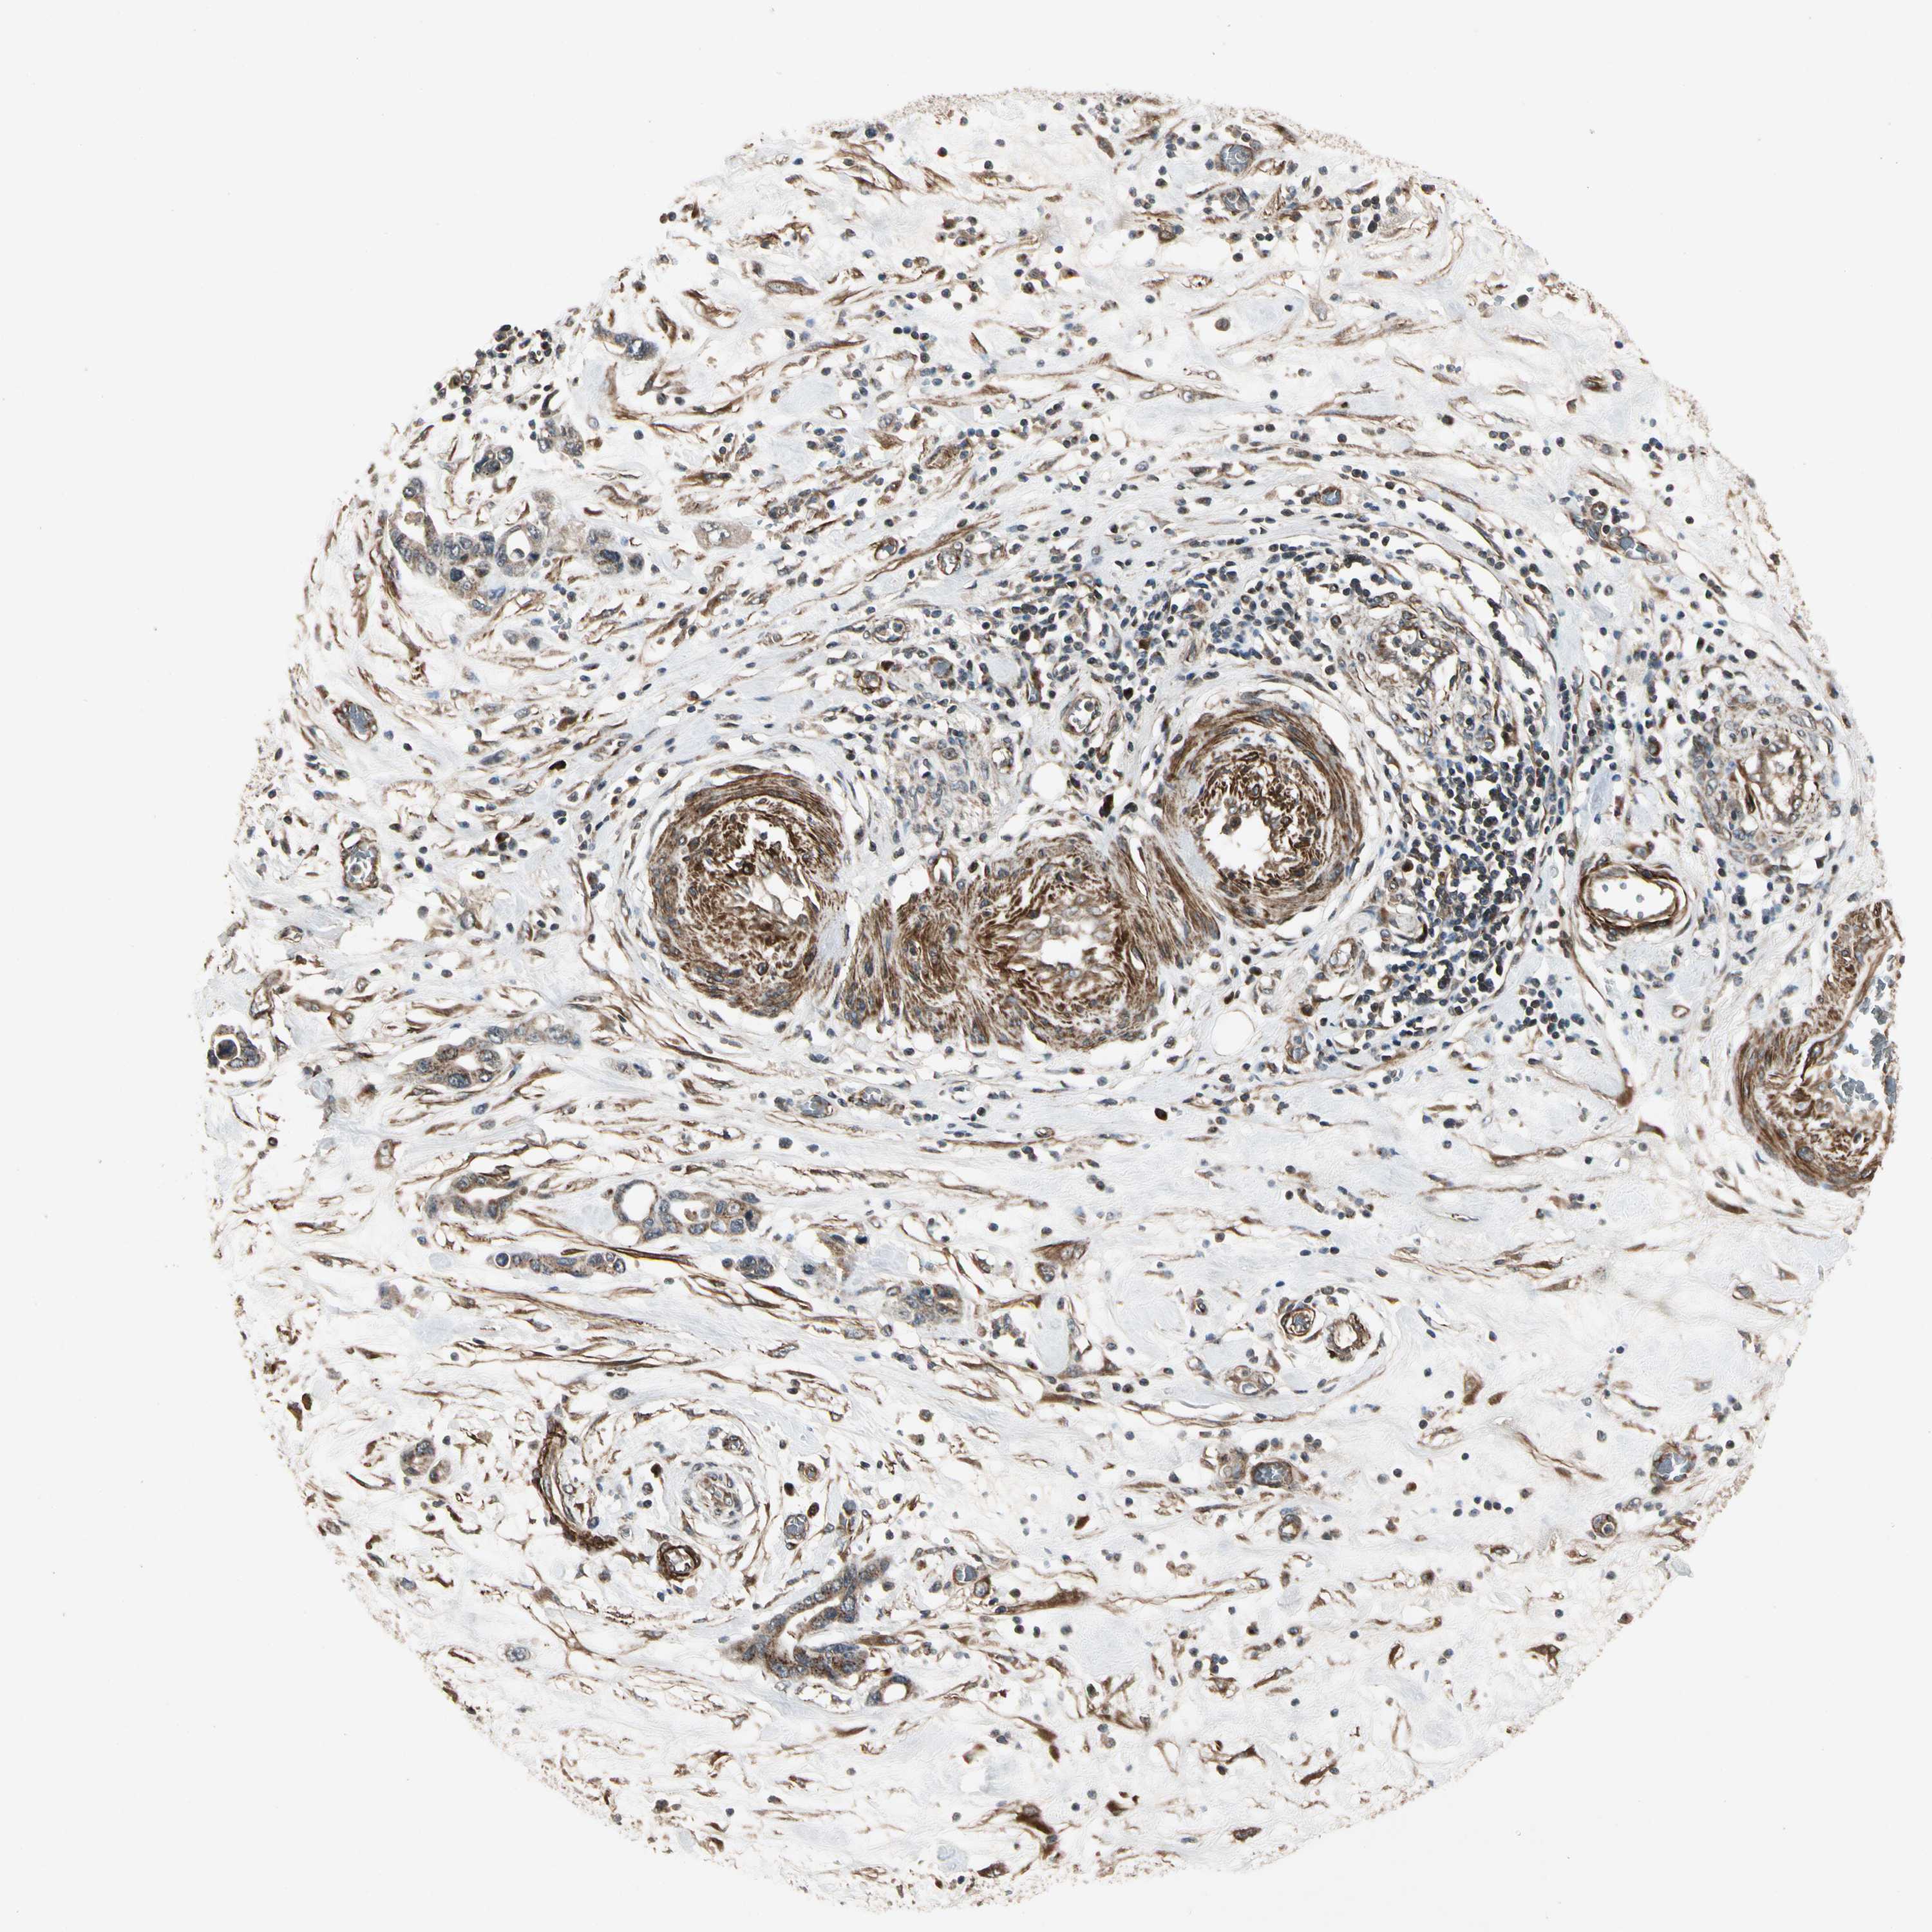

PANCREATIC CANCER - Protein expressioni

A mouse-over function shows sample information and annotation data. Click on an image to view it in a full screen mode. Samples can be filtered based on level of antibody staining by selecting one or several of the following categories: high, medium, low and not detected. The assay and annotation is described here.

Note that samples used for immunohistochemistry by the Human Protein Atlas do not correspond to samples in the TCGA dataset.

Antibody stainingi

Antibody staining in the annotated cell types in the current human tissue is reported as not detected, low, medium, or high, based on conventional immunohistochemistry profiling in selected tissues. This score is based on the combination of the staining intensity and fraction of stained cells.

Each image is clickable and will lead to virtual microscopy that enables deeper exploration of all samples and also displays staining intensity scores, fraction scores and subcellular localization as well as patient and tissue information for each sample.

Antibody HPA007034

Antibody HPA007093

Staining

High

Medium

Low

Not detected

Intensity

Strong

Moderate

Weak

Negative

Quantity

>75%

75%-25%

<25%

None

Location

Nuclear

Cytoplasmic/membranous

Cytoplasmic/membranous,nuclear

Adenocarcinoma, NOS